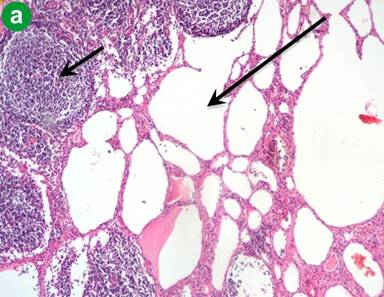

Macroscopically, the mass had a cystic and lobulated appearance (Figure 4). The microscopic findings of the mass are shown in Figure 5. Furthermore, the diagnosis of a cystic lymphangioma of the pancreas was confirmed by immunohistochemistry which showed CD3 and factor VIII positivity for cells lining the dilated channels in a sample of the head of the pancreas.

|

Figure 5 a. Aggregates of lymphoid cells (short arrow) adjacent to closely packed lymphatic channels (long arrow). (H&E staining; low power magnification: x10). b. Pancreatic tissue (short arrow) and lymphatic channels (long arrow). The background is formed by mesodermal tissue. (H&E staining; low power magnification: x10). |